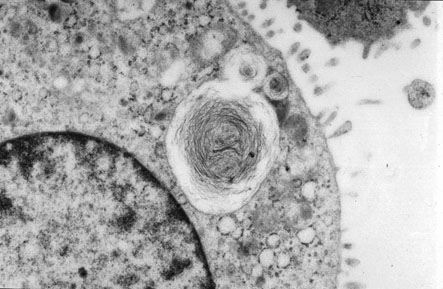

Electron micrograph of type II pneumocyte with nucleus in upper right corner and lamellar body (surfactant) in middle.